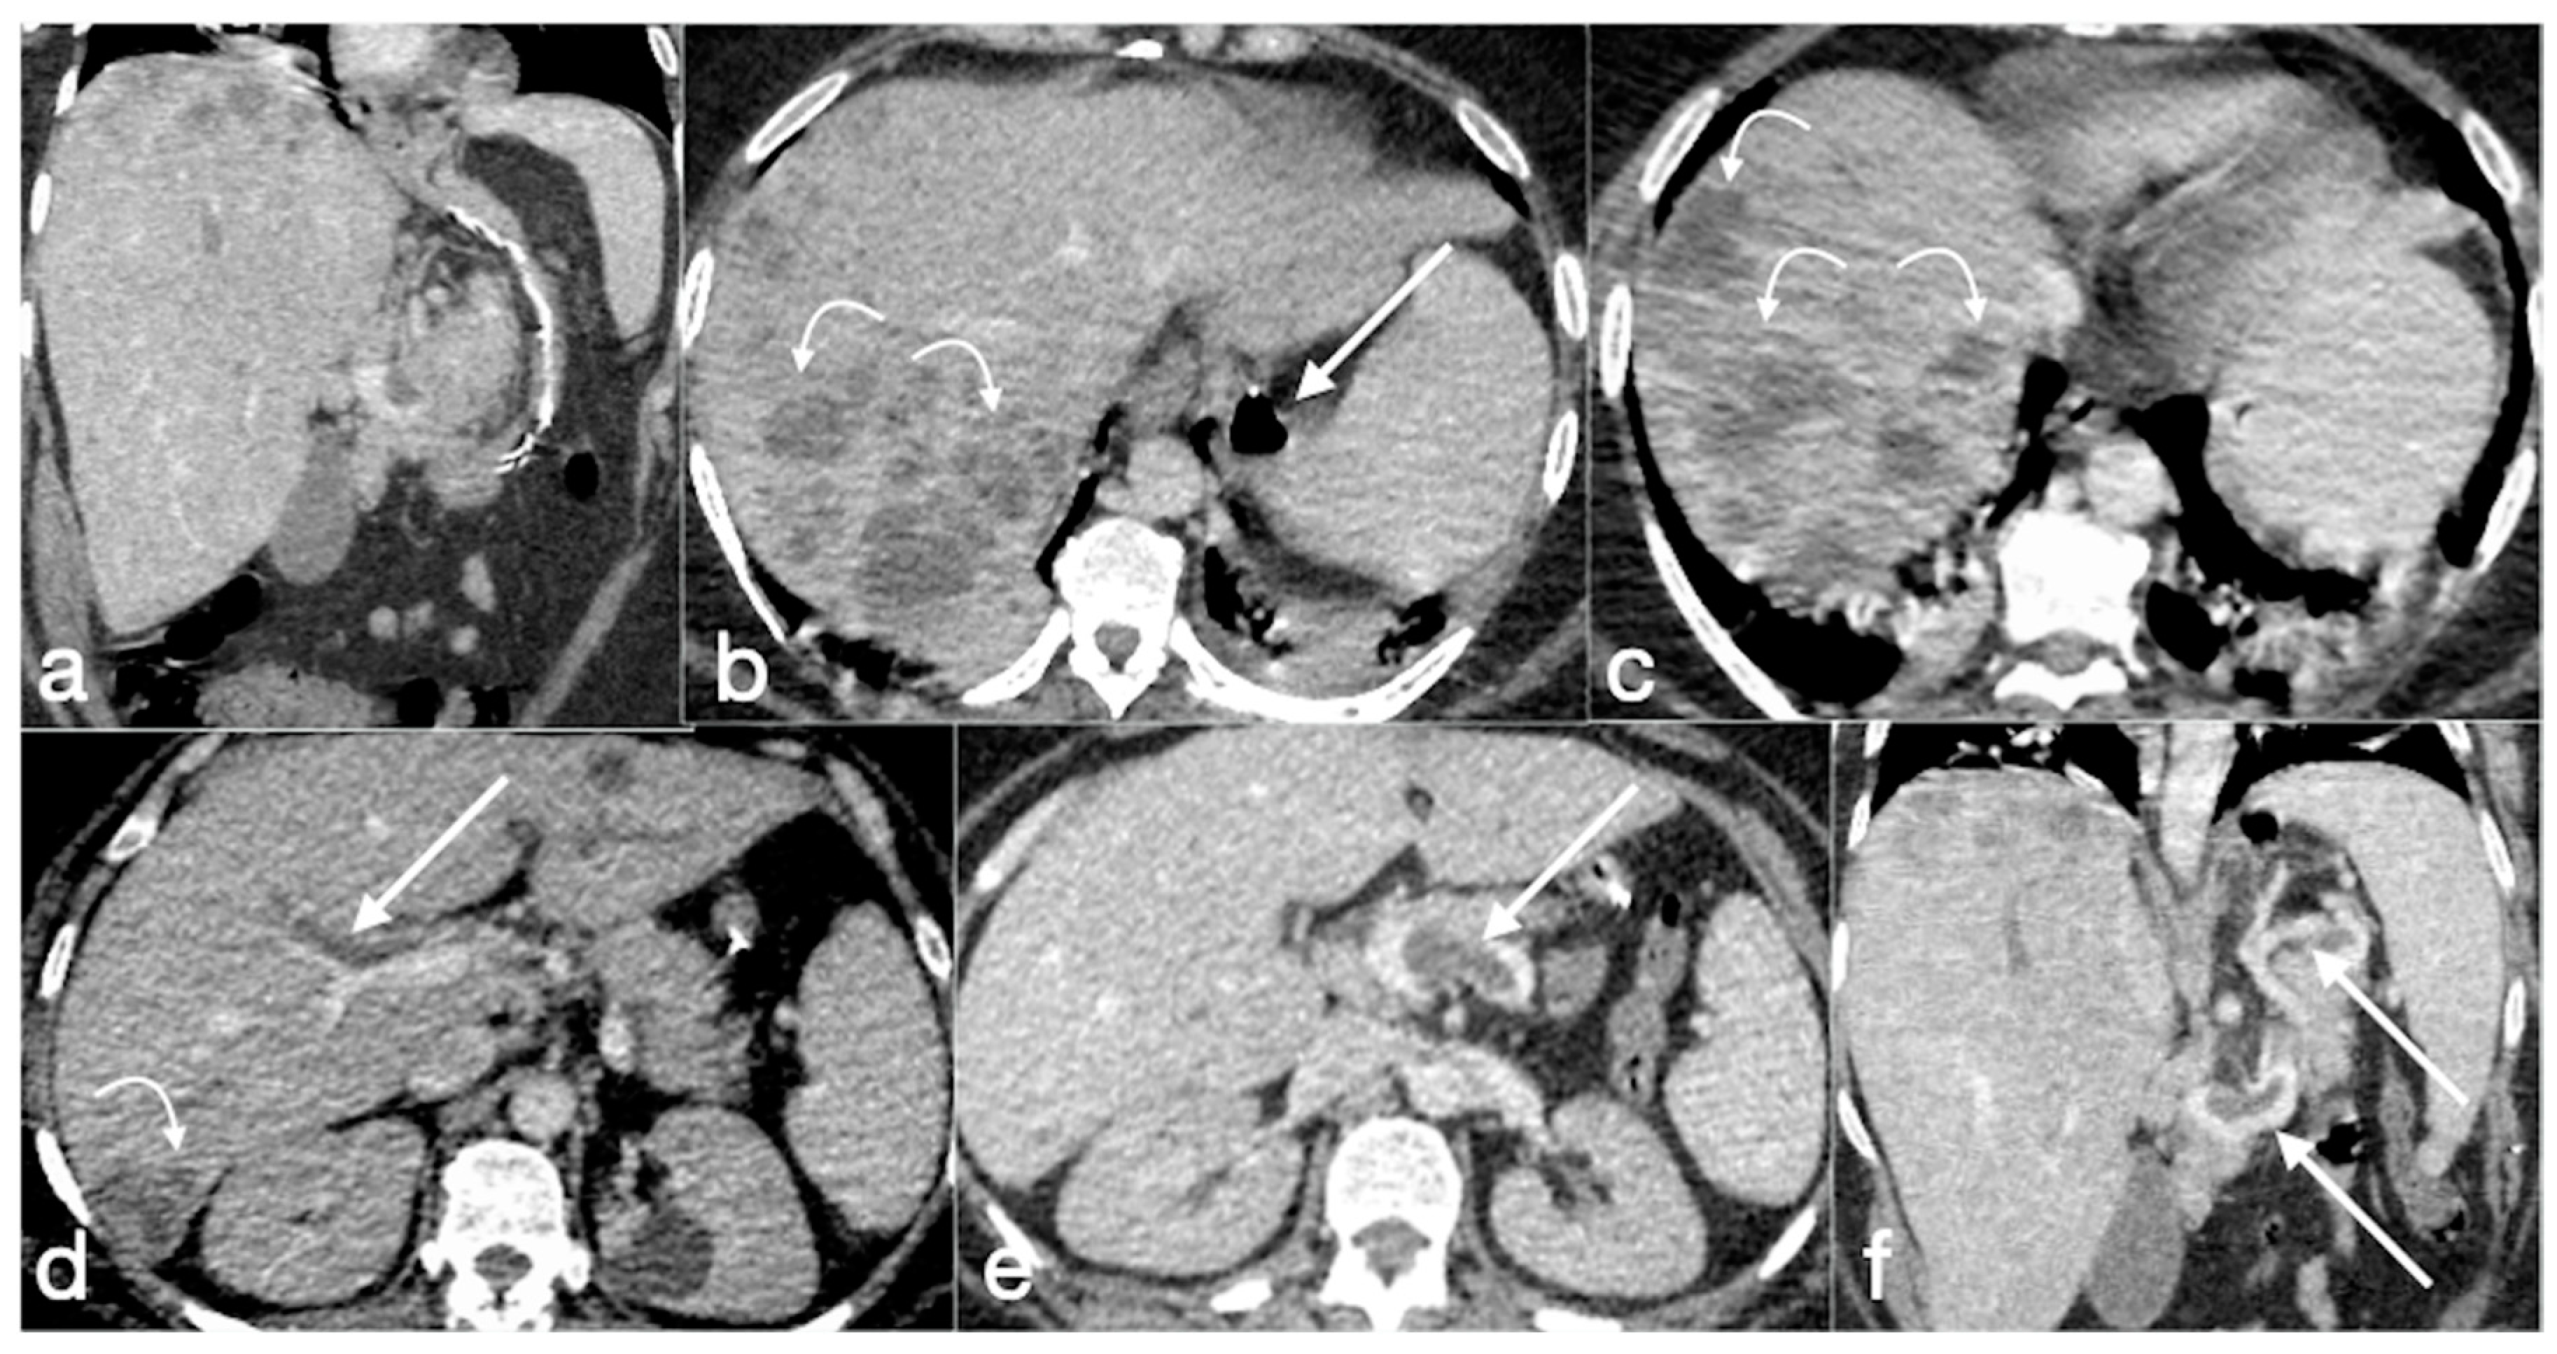

Figure 19. Patient 1. Porto-spleno-mesenteric venous thrombosis and colonic ischemia after sleeve gastrectomy. A 37-year-old female patient underwent sleeve gastrectomy. The patient came to the emergency department complaining of abdominal pain and fever. See the surgical gastric suture (a, coronal oblique view), the enlarged and thrombosed spleno-portal lumen (b, axial view; c, coronal oblique view, straight arrows), the consequential mesenteric congestion (d, axial view; e, coronal view, curved arrows), and the colonic ischemia (d, axial view; e, coronal view, circles). In the coronal view (e), the thrombosis that extends to the superior mesenteric vein lumen can be seen best. The patient was treated with multiple session of transhepatic catheter-directed thrombolysis.